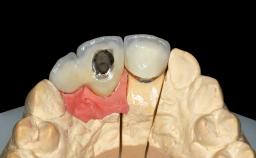

Replacement of Four Incisors with a Fixed Partial Denture on Two Narrow-Neck Implants after Implant Failure

| Prosthesis Type | FDP |

| Retention | Screw-retained, with splinted implants Screw-retained, with splinted implants |

| Soft Tissue Contour and Volume | Significantly deficient |